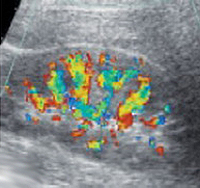

Под хронической почечной недостаточностью (ХПН) понимается синдром, при котором у человека отмечается длительное нарушение работы почек. Если у больного наблюдается сбой в работе выделительной системы на протяжении 3-х месяцев и более, то можно говорить о развитии у него ХПН.

В основе патогенеза лежит прогрессирующая гибель нефронов. Вначале почечные процессы становятся менее эффективными, затем нарушается функция почек. Морфологическая картина определяется основным заболеванием. Гистологическое исследование свидетельствует о гибели паренхимы, которая замещается соединительной тканью.